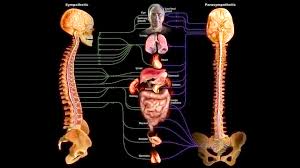

قیمت: 34٬000 تومان - دسته بندی فایل: تحقیقپاورپوینت دستگاه عصبی خود مختار (ppt) 11 اسلاید

فروش ویژه پاورپوینت حرفه ای دستگاه عصبی خود مختار / تعداد اسلاید: 11 اسلاید